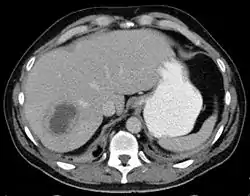

![]() صورة مقطعية لخراج الكبد صورة مقطعية لخراج الكبد | |